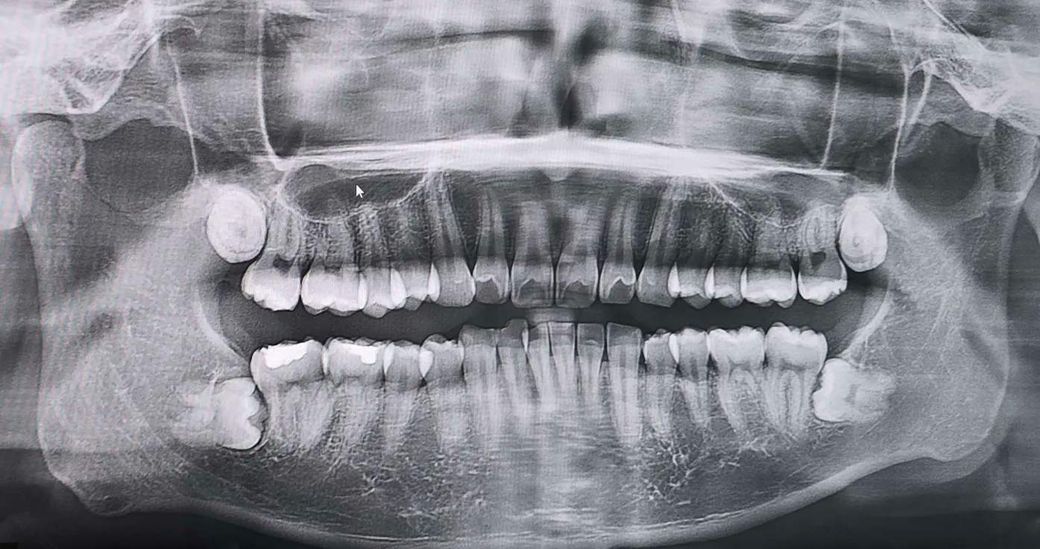

하악 완전 매복 사랑니 발치 해야될까요?

얼마 전 촬영했던 xray입니다.

상악쪽 두개는 나오고 있어서 발치를 조만간 하려고 하는데,

하악쪽도 발치가 필요한 경우 동시에 같이 발치하는게 좋지 않을까 싶어 질문 해봅니다.

90도로 뼈 밑에 있는 것처럼 보이고 앞 어금니와에 공간도 살짝 있는 것 같아서 필요한지 궁금합니다.

입 안에서 봤을 때도 나와있지 않고 불편감도 없는 상태입니다.

아래치아의 경우에는 난이도가 아주 높은 편이라 불편감이 없다면 꼭 뺄 필요는 없어보입니다.

하악의 사랑니의 경우는 특별한 이유가 없다면 발치를 안하셔도 크게 문제가 되진 않을것같습니다.

매복이 아주 깊은 상태입니다. 지금은 별 증상이 없어도, 옆 어금니 뿌리를 녹이거나 충치를 유발할 확률이 있습니다. 대학병원 가셔서 발치 상담해보세요

사진으로 봤을 경우에는 완전히 매복되어 있고 다른 조직에 문제를 발생시키지 않습니다. 하지만 오른쪽 아래 사랑니의 경우에는 앞에 있는 지하에 지지를 하는 치조골을 많이 침범한 상태이기 때문에 발치를 해주는 것이 좋을 수도 있습니다.

자세한 확인을 위해서 치과에서 진료를 받아보는 것을 권유드립니다.